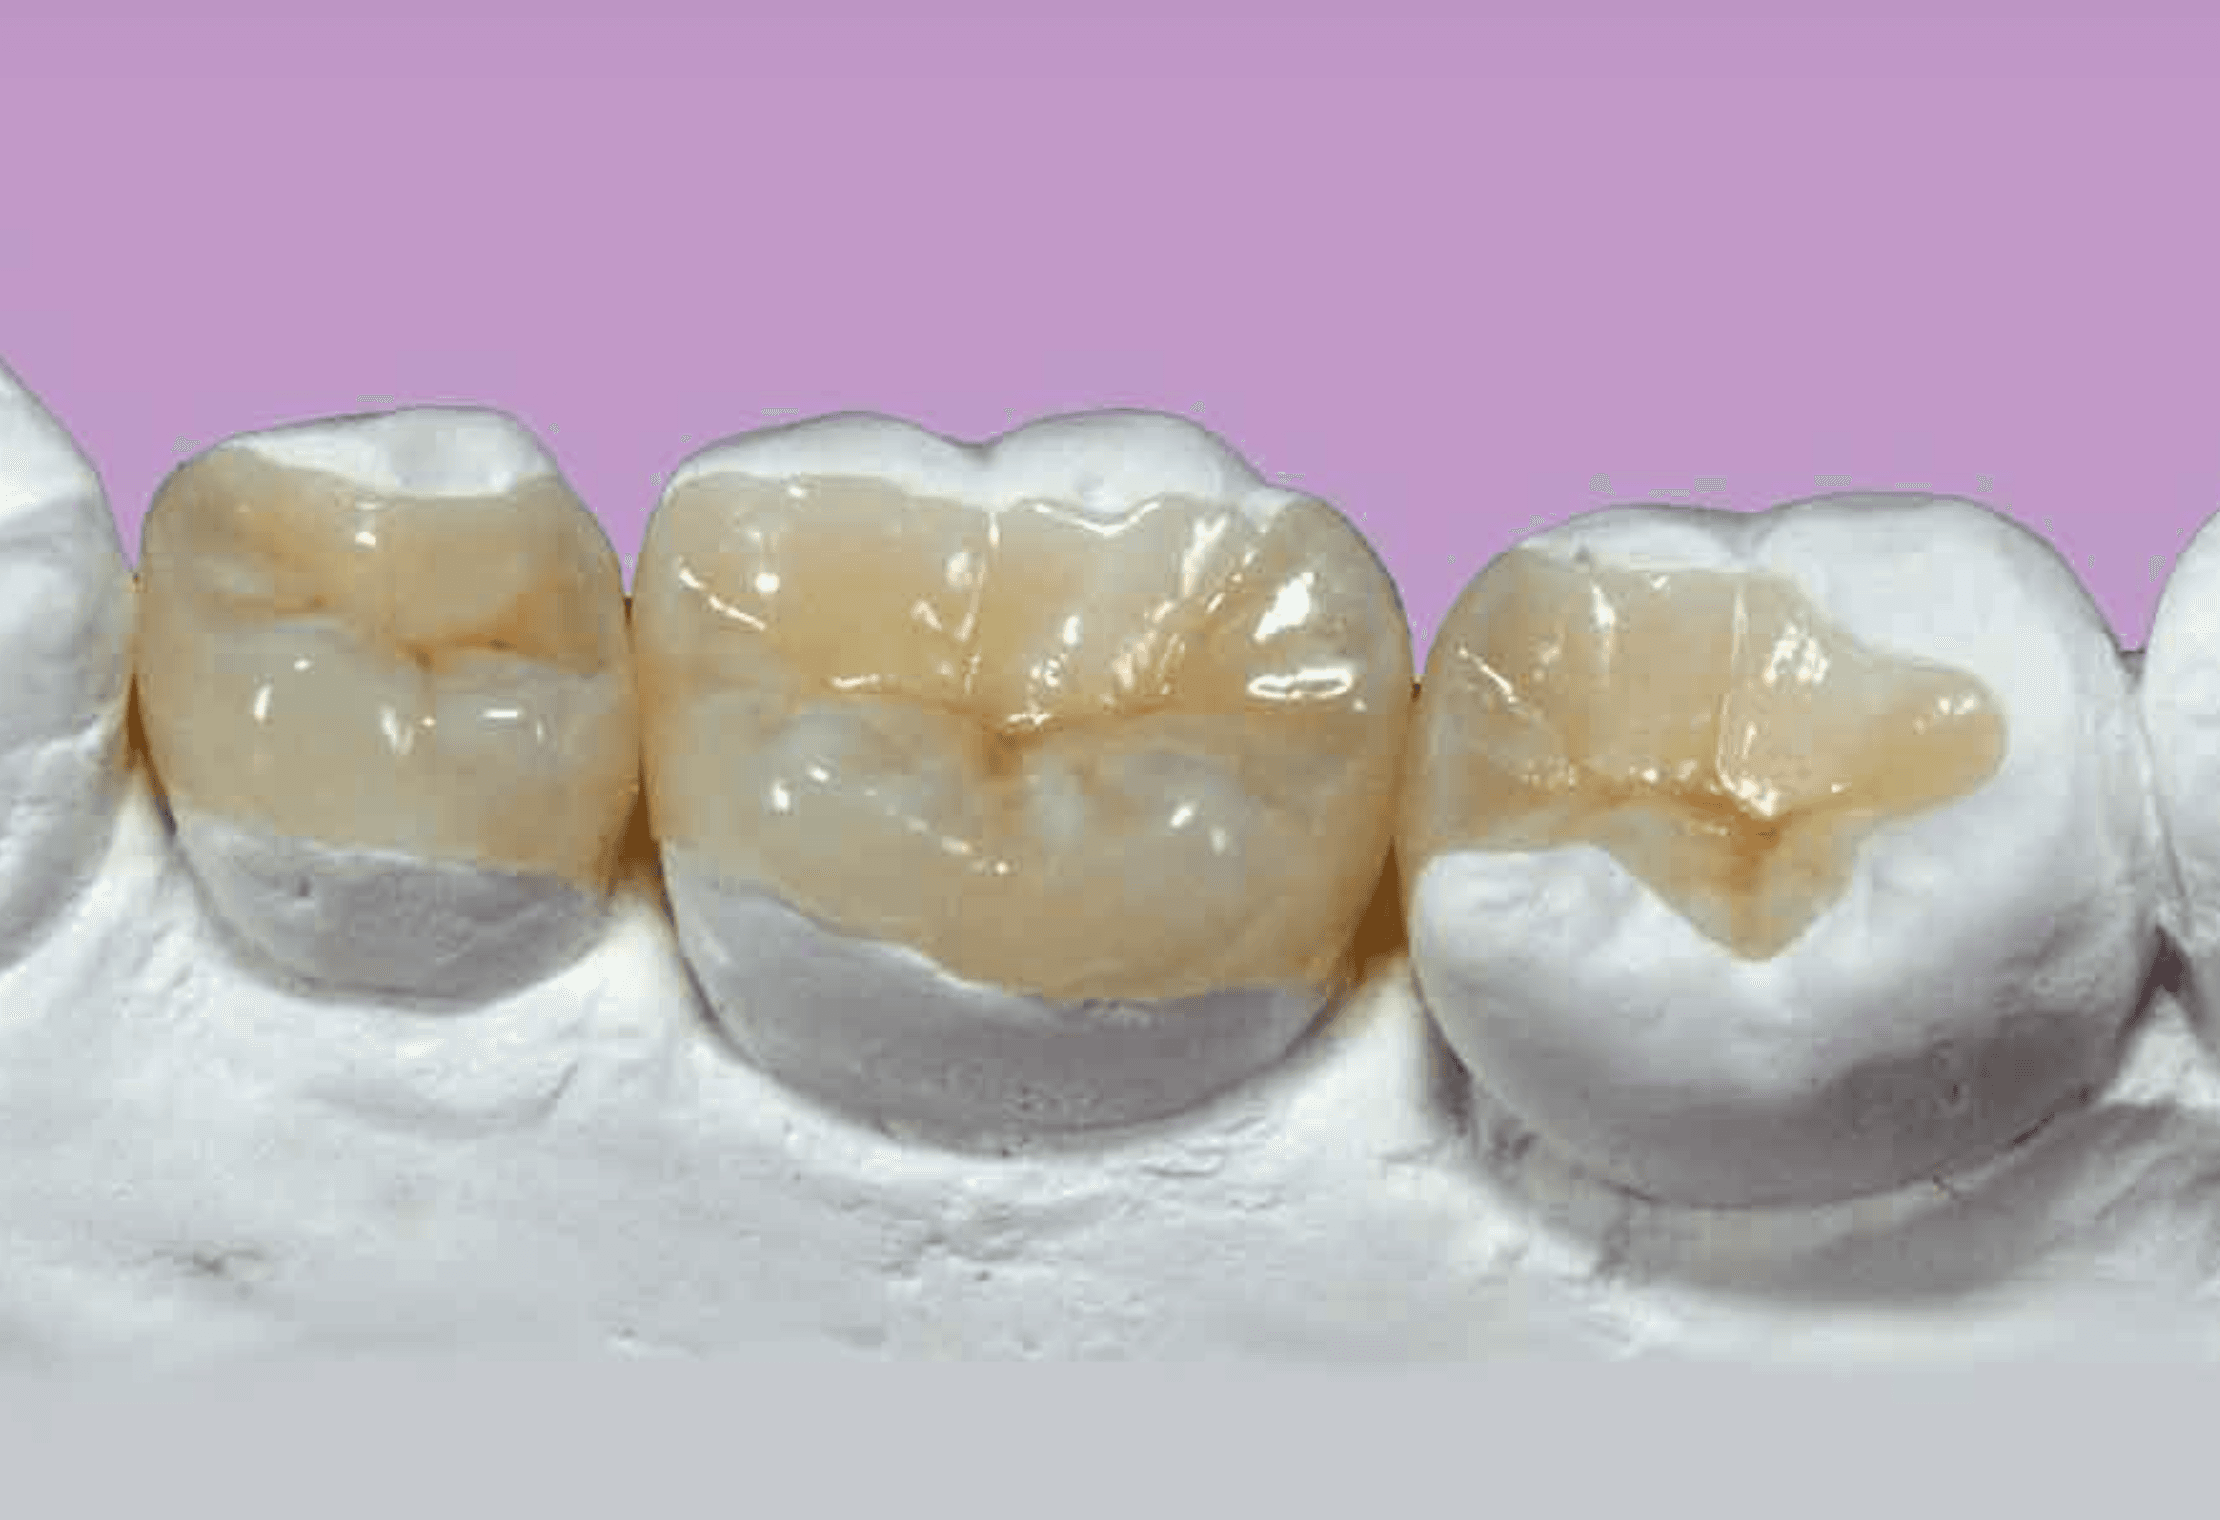

충치 치료

One Day 인레이 – 하루 만에 끝내는 충치 치료

충치 치료, 더 이상 미루거나 두려워하지 마세요.

직장‧학교‧가사로 바쁜 요즘, 2-3회 내원은 큰 부담이 됩니다.

플란트구강악안면외과 치과는 3D 디지털 스캔+설계+밀링 시스템으로 인레이 제작-부착을 당일에 완료해 시간을 확 줄였습니다.

빠르지만, 정밀합니다

정확한 디지털 스캔으로 치아 형태를 ㎛ 단위까지 캡처

CAD/CAM 설계로 틈새 없이 맞춤 제작

세라믹 블록을 밀링해 색·투명도까지 자연스럽게 구현

의사가 즉시 적합도·교합을 확인하니 추가 조정 필요 거의 없음

One Day 인레이의 핵심 장점

시간 절약 | 단 한 번 방문으로 치료·복귀

높은 내구성 | 디지털 설계-가공으로 강도·정밀도 향상

심미성 | 치아 색상과 자연스럽게 어우러져 앞니도 OK

편리한 예약 | 탄력 스케줄 운영, 퇴근 후·주말 진료 가능

충치 때문에 스케줄을 비우기 어렵다면 One Day 인레이로 하루 만에 해결하세요.

용현동 플란트구강악안면외과 치과가 빠르고 정밀한 디지털 치료로 당신의 시간을 지켜드립니다.